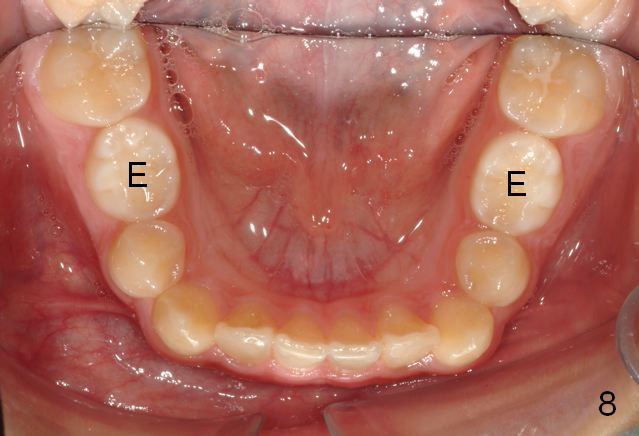

A 11-year-old boy has shorter lower 1/3 face (Fig.1,2) with light concave profile, especially the lower lip (Fig.3).  There is anterior deep bite (Fig.4) with Class II posterior occlusion (Fig.5,6).  UL2 is microdontia (Fig.7 *), while the Lower Es are retained (Fig.8).  Preop (2015_01_07) Ceph (Fig.9) and Pan (Fig.10) show ectopic L7s and congenitally missing L5s.

Brackets were placed on 2015_09_06 (Fig.11-13, Phase I pre-orthopedic tooth movement, leveling in advance of Herbst appliance therapy using ankylosed Es).   Six months later (Fig.14-16), LR7 did better, LL7 did not and will need intervention. But intrusion of L 3-3 looks good.